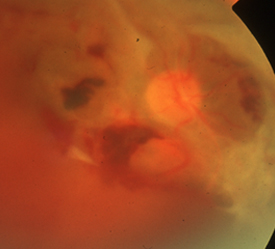

④増殖網膜症

虚血部分に酸素や栄養を送り込もうと、新生血管が網膜の表面や硝子体に伸びてきます。薄い膜状の増殖膜が形成されたり、新生血管が破れることで硝子体出血、増殖膜が網膜を牽引することで網膜剥離が生じます。